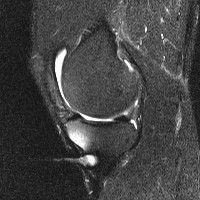

무릎 mri 간단히 봐주실 수 있으시나요 ㅠㅠ

안녕하세요 8년전 십자인대 수술하고 최근 무리한 운동에 무릎 불편감이 생겨서

mri 찍었습니다.

진단결과는 첫 찍은 병원에서 활액막염 이라는 진단을 받았습니다. 혹시 봐주실 수 있으실까요?

올라온 MRI가 단편적이라서 정확한 진단에 어려움이 있지만 십자인대에는 큰 이상이 있지는 않은것 같으며, 무릎관절내 물이 있는 것으로 보아 활액막염의 진단이 맞을 것 같습니다.

하지만 단편적인 영상이기 때문에 촬영병원에서 정확한 판독지 등을 받으시는 것이 좋겠습니다.